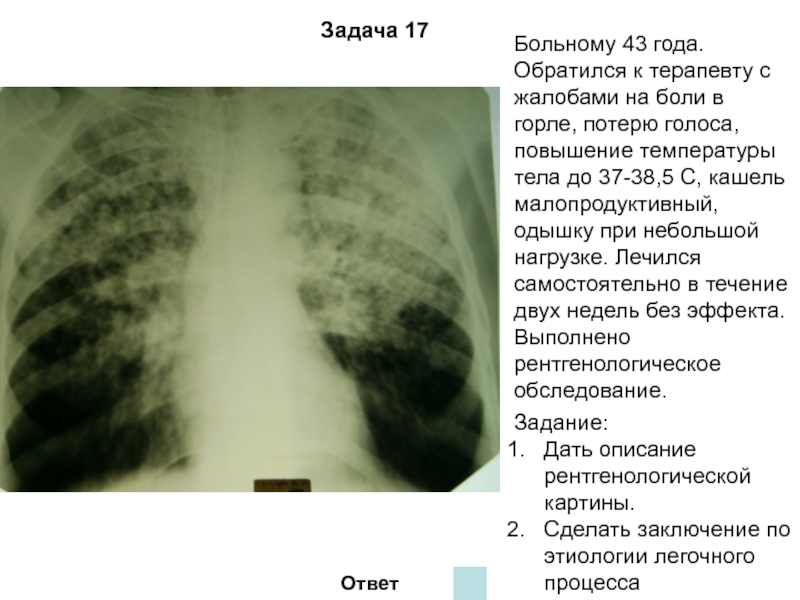

Симптомы и лечение инфильтративного туберкулеза легких

Раздел: Снимки-откровения